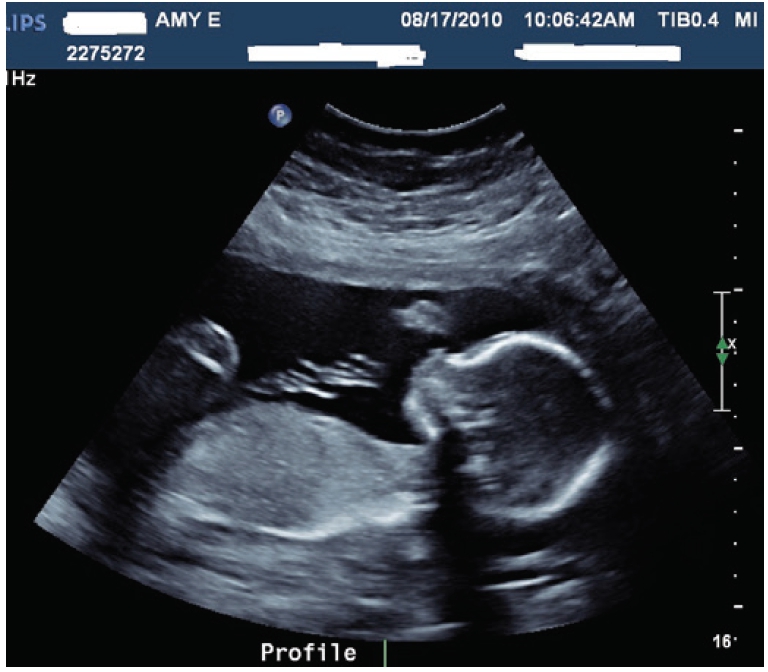

În materie de diagnostic medical, primii pași AI au fost făcuți în imagistica ficatului, a sânului și a tiroidei. În ultimii ani cercetarea și producătorii de aparatură de diagnostic cu ultrasunete s-au axat pe dezvoltarea AI și în ecografia fetală. Această zonă a fost și rămâne o provocare pentru diagnostic, cu dificultățile inerente legate de poziția și mobilitatea fetală, mărimea fetală variabilă, de diferențele între cantitatea de lichid amniotic și poziția placentei, particularitățile țesuturilor materne.

Literatura de profil a ultimilor 3-5 ani indică date concrete, ce sugerează utilizarea AI în ecografia de prim trimestru. Diferite publicații descriu utilizarea AI în zone cum ar fi: placentația de la normal la patologic, biometria fetală, anatomia fetală - în special cea craniană și cardiacă, evaluarea pulmonară, recunoașterea patologiilor. Chiar dacă există limite importante ale utilizării ca diagnostic, asistența AI este clar demonstrată.

Pe de altă parte, progresul aparaturii, a calității imaginii ecografelor, a permis producătorilor de profil lansarea pe piață de noi soft-uri cu AI. Dacă în urmă cu circa 15 ani cei interesați de ecografia fetală erau bucuroși să utilizeze ecografele cu primele măsurători automate, astăzi AI identifică secțiunile standard și le salvează automat real-time, sau prelucrează automat un volum 3D cu indicarea secțiunilor standardardizate prin ghiduri. AI indică calitatea secțiunilor achiziționate de ecografist, crește eficiența, indică numărul omisiunilor, reduce variabilitatea interobservațională, sugerează anomaliile fetale și în general ridică calitatea ecografiei obstetricale. Dacă la aceasta adăugăm aparatele de simulare cu AI, ce pot avea o multitudine de anomalii congenitale pe care ecografistul le scanează virtual, putem înțelege impactul în training pentru generațiile tinere.